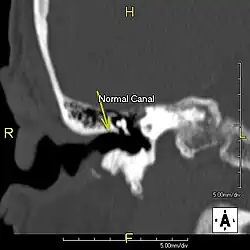

L'exostose du surfeur ou oreille de surfeur est une exostose, c'est-à-dire une croissance osseuse anormale, qui pousse vers l'intérieur du conduit auditif[1]. L'os entourant le conduit auditif réagit à l'agression thermique et mécanique de l'eau froide et de ses turbulences, par une nouvelle croissance osseuse qui a pour effet de resserrer le conduit auditif.

Du fait de la réduction du diamètre du conduit auditif, l'eau et le cérumen peuvent rester piégés entre la masse osseuse et le tympan et provoquer ainsi une infection comme une otite externe, particulièrement douloureuse.

Le contact de l’os avec le tympan peut provoquer des acouphènes[4]. Si rien n'est fait, les excroissances osseuses peuvent conduire à une obturation du conduit auditif et à une perte d'audition[1].